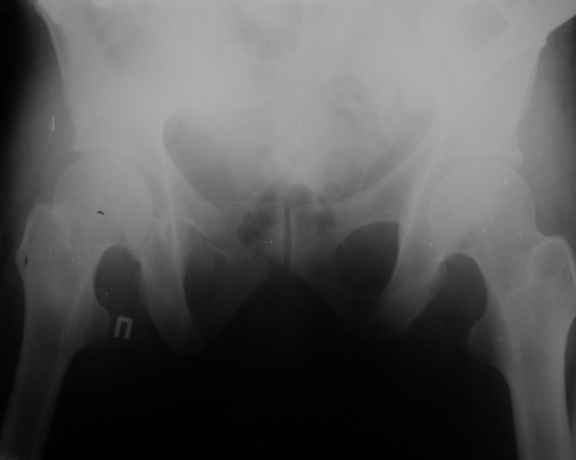

Можно посмотреть на нынешние снимки таза в аппарате, фас и inlet?

Отправитель: Владимир Бахарев 16 Ноябрь 2006, 12:13

Снимки вот

> (перелом лонной, седалищной костей справа . Разрыв КПС слева)

может быть и двустороннее повреждение задних отделов

по представленным рентгенограммам понять почти ничего невозможно из-за низкого качества, снимки идут в динамике? Для уточнения характера повреждения таза необходимо сделать хотя бы "inlet". повреждение представляется вертикально-нестабильным, в этом случае устранить краниальное и, возможно, передне-заднее смещение "передней рамой" невозможно и дело тут не в жесткости АВФ. Кольцевой опорой можно сделать все что угодно.